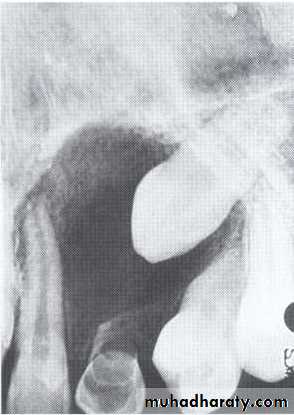

• 2.Position in the jaws:

• - Epicenter of the lesion is above the mandibular canal-odontogenic in origin .

• - Epicenter -below lDC- non odontogenic

Cystic ameloblastoma displaced IDC (odontogenic origin)

Epicenter coronal to tooth(odontogenic epithelium )